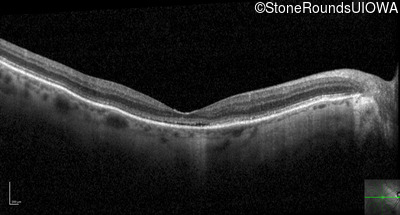

Optical Coherence Tomography - Left - 20/400

Exemplar / OCT Stack